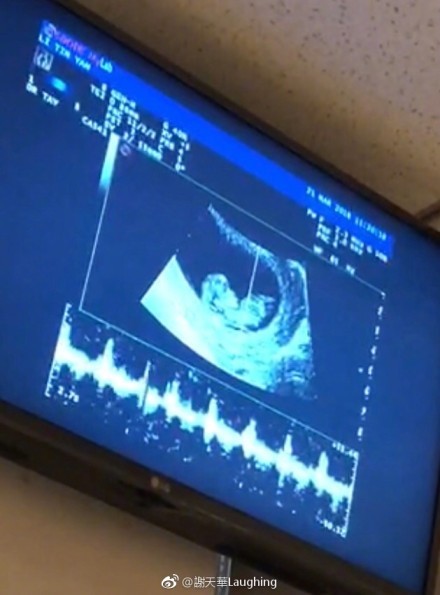

谢天华老婆怀二胎 晒宝宝B超照,网友:看你的电影长大

4月10日,香港著名影星谢天华在社交媒体上晒图,并配文:“今年将会迎接家里的新成员,感恩感恩!天天要做哥哥了,也辛苦了妈妈。”照片是谢天华妻子怀二胎的b超图,可以看出一个小宝宝在妈妈肚中,画面十分有爱。